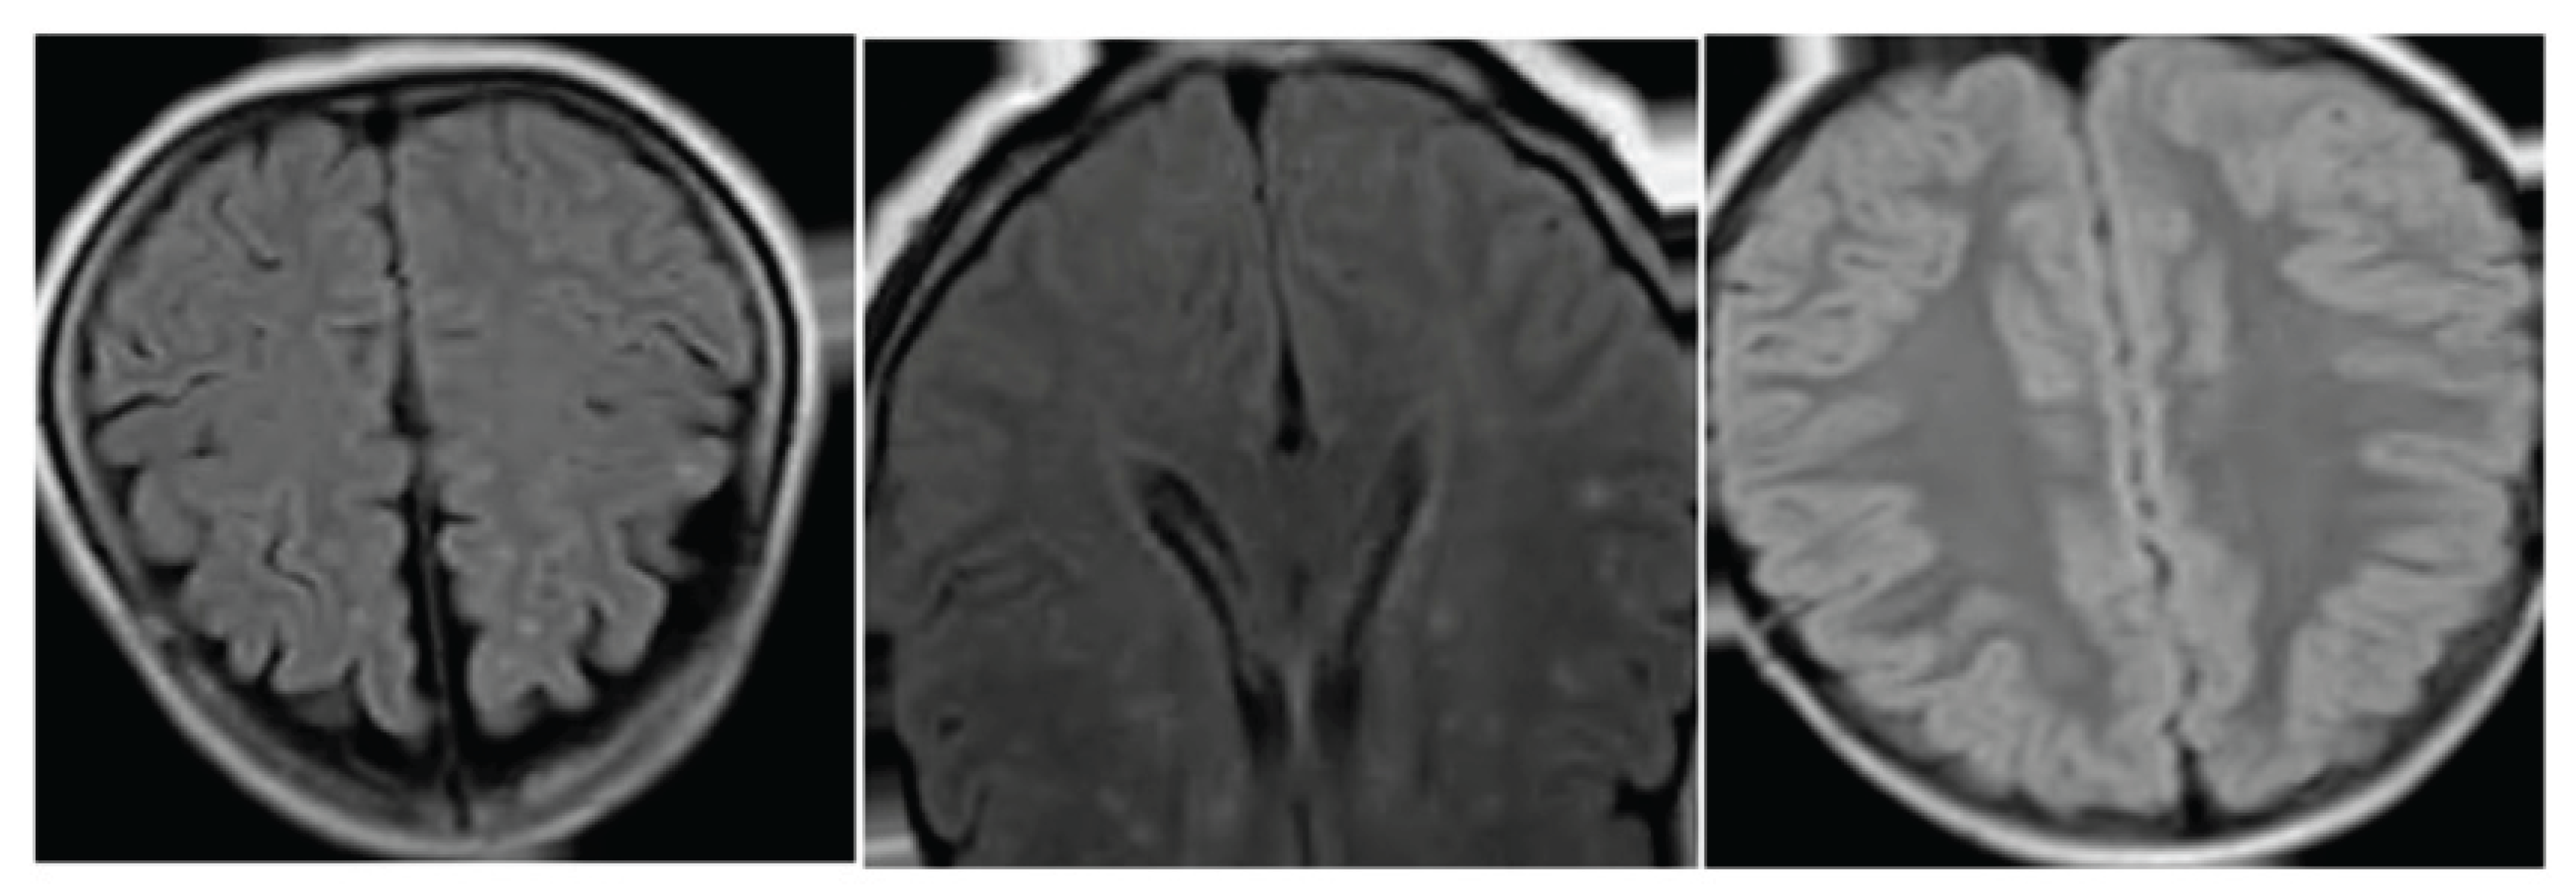

Figure 2. Region-wise Dice and small-region IoU, with examples of periventricular and deep WMH segmentation.

3.2. Region-Wise Evaluation and Detection of Small Deep Lesions

Region-wise evaluation shows that SPAN-WMH improves segmentation in both periventricular and deep areas. The larger gain in deep regions (+0.099 Dice) suggests that structural priors help the model detect small and scattered lesions that are often overlooked by intensity-based networks [16]. Small-region IoU increases by 12.1%, which shows better retention of tiny lesions that tend to be eroded during post-processing in many U-Net-based methods.